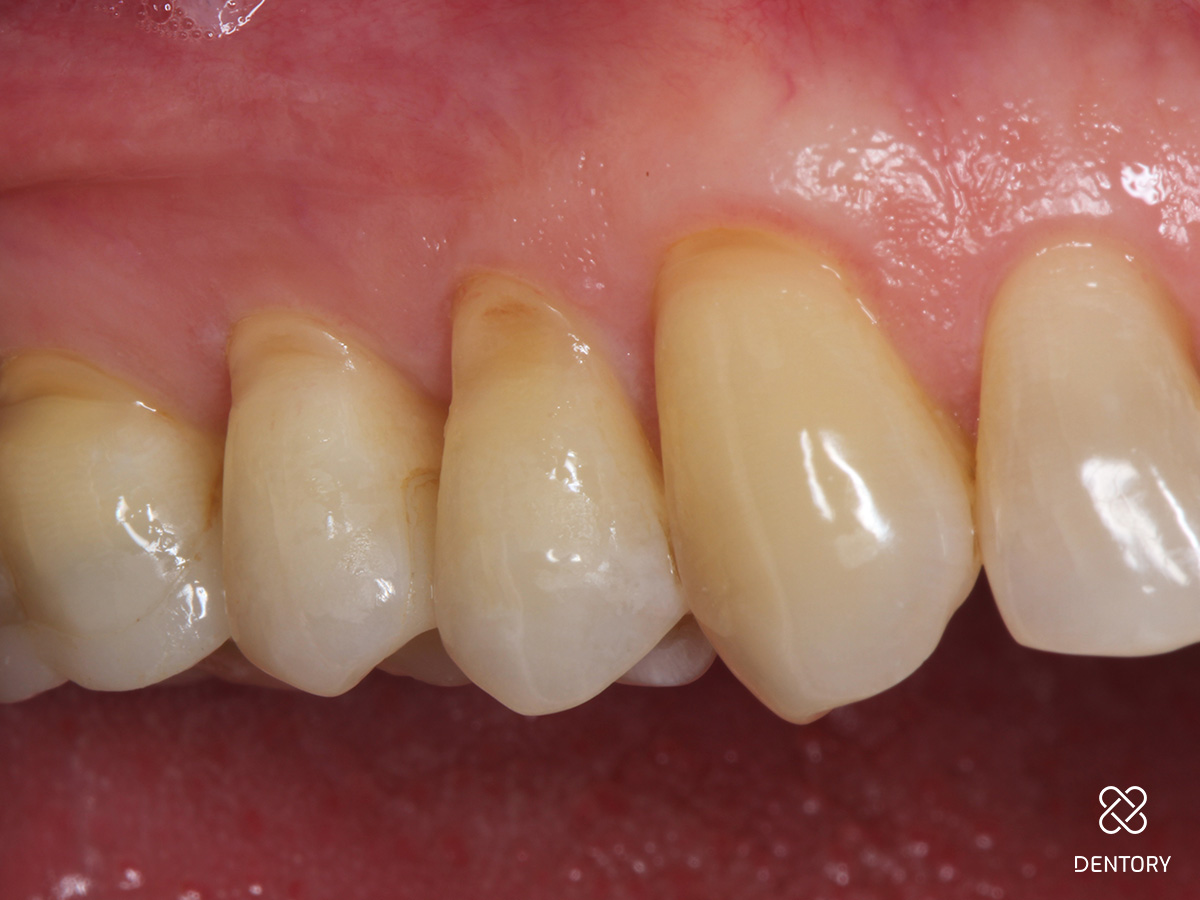

Abbildung 8

Beim Kontrolltermin nach 2 Wochen.